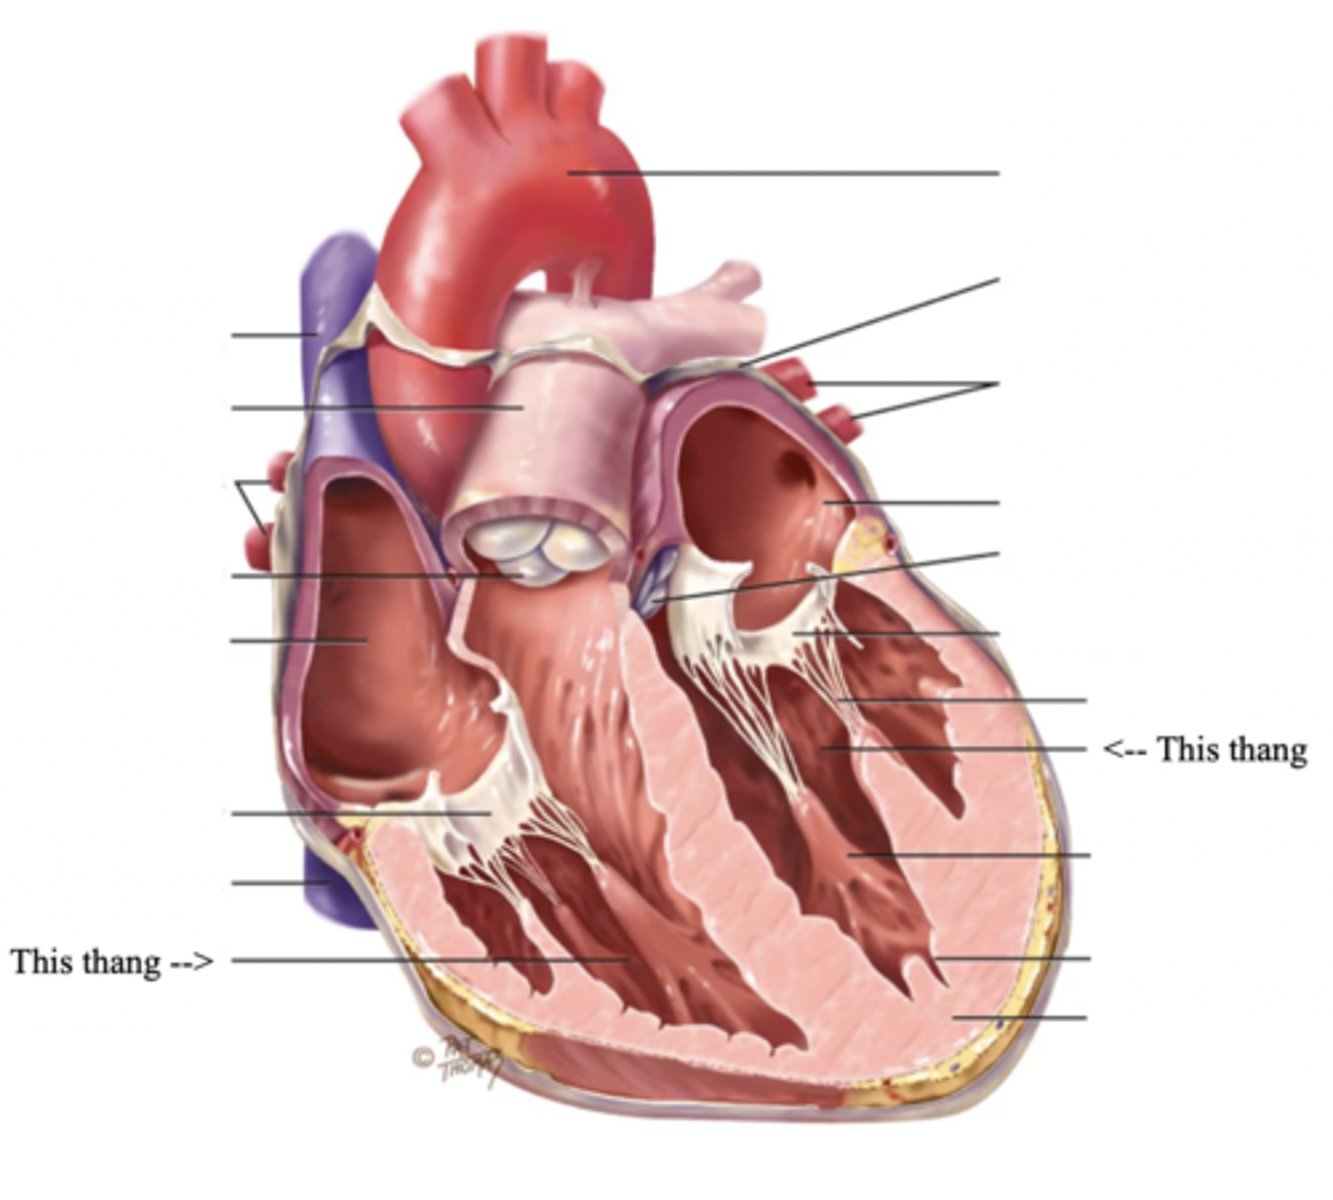

Anatomy of the Heart

Myocardium

The muscular wall of the heart; does the pumping

Endocardium

The thin layer of endothelial tissue that lines the inner surface of the heart chambers and valves

2 Types of Chambers in the Heart

- Atrium

- Ventricles

Atrium (2)

A thin-walled reservoir for holding blood, located at the upper chamber of the heart

Ventricle (2)

The thick walled muscular pumping chamber of the heart located at the bottom chamber of the heart

2 Main Types of Valves of the Heart

- Atrioventicular

- Semilunar

Atrioventricular Valves (AV) (2)

The valves that separate the atria and the ventricles

The 2 Atrioventicular Valves of the Heart

- Tricuspid

- Mitral

Tricuspid Valve

- The right AV valve separating the right atrium from the right ventricle

- Connected by 3 chordae tendinae

Mitral (Bicuspid) Valve

- The left AV valve separating the left atrium from the left ventricle

- Connected by 2 chordae tendinae

Chordae Tendinae

Fibers (heart strings) attatched to the tricuspid and mitral valve which pull it closed when papillary muscles contract, preventing back flow of blood

Semilunar Valves (SV) (2)

Valves located between the ventricles and the pulmonary arteries and aorta

The 2 Semilunar Valves of the Heart

- Pulmonic

- Aortic

Pulmonic Valve

The SV valve of the right side of the heart

Aortic Valve

The SV valve of the left side of the heart